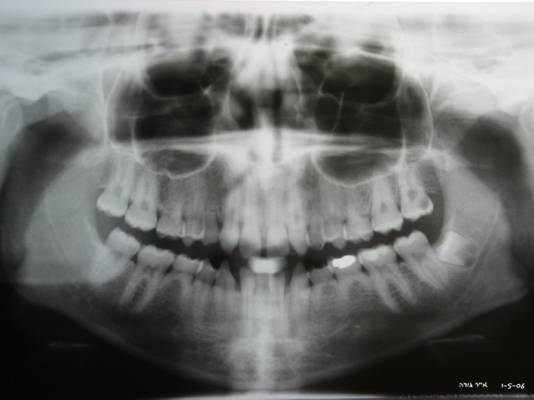

jeune fille de 19 ans avec agenesies:

(18)15,12,22,25(28)

(48)45,42,32,34,35

je la vois dans 3 semaines en premiere consultation au cabinet du specialiste en implanto